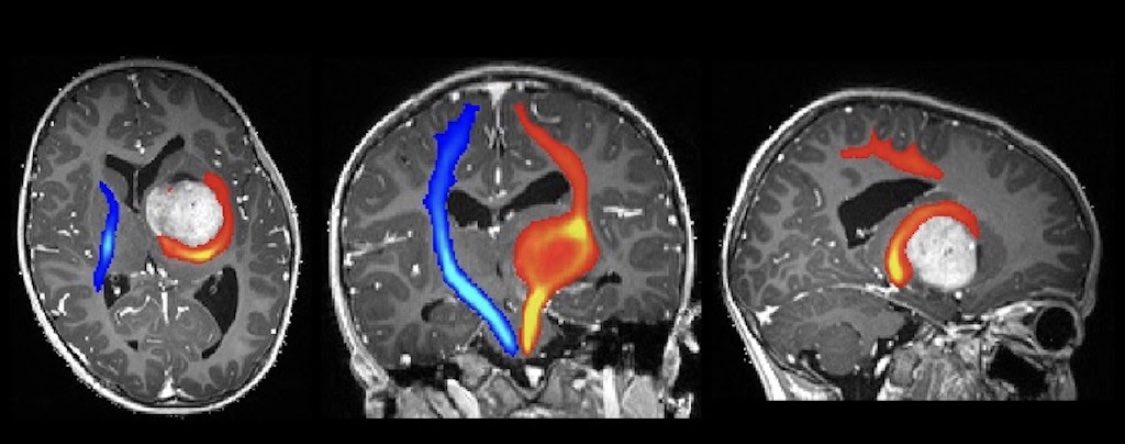

In keeping with the vast literature on this topic, most neurosurgeons used tractography as an adjunct for brain tumour resection, like in the case below (2/5)